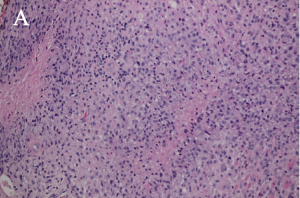

There are four subtypes of adult xanthogranulomatous disorders and one juvenile xanthogranuloma. Xanthogranulomatous disorders are non-Langerhans histiocytoses. Like xanthomas, the lesions in these disorders contain foam cells; they differ from xanthomas in the presence of Touton giant cells, a type of multinucleated giant cell with a high lipid content, and varying degrees of fibrosis and necrosis (Images 3A, 3B).

Xanthogranulomas differ from xanthomas by the presence of Touton giant cells, a type of multinucleated giant cells with high lipid content, and areas of necrosis (Images 3A, 3B, 4A, 4B).